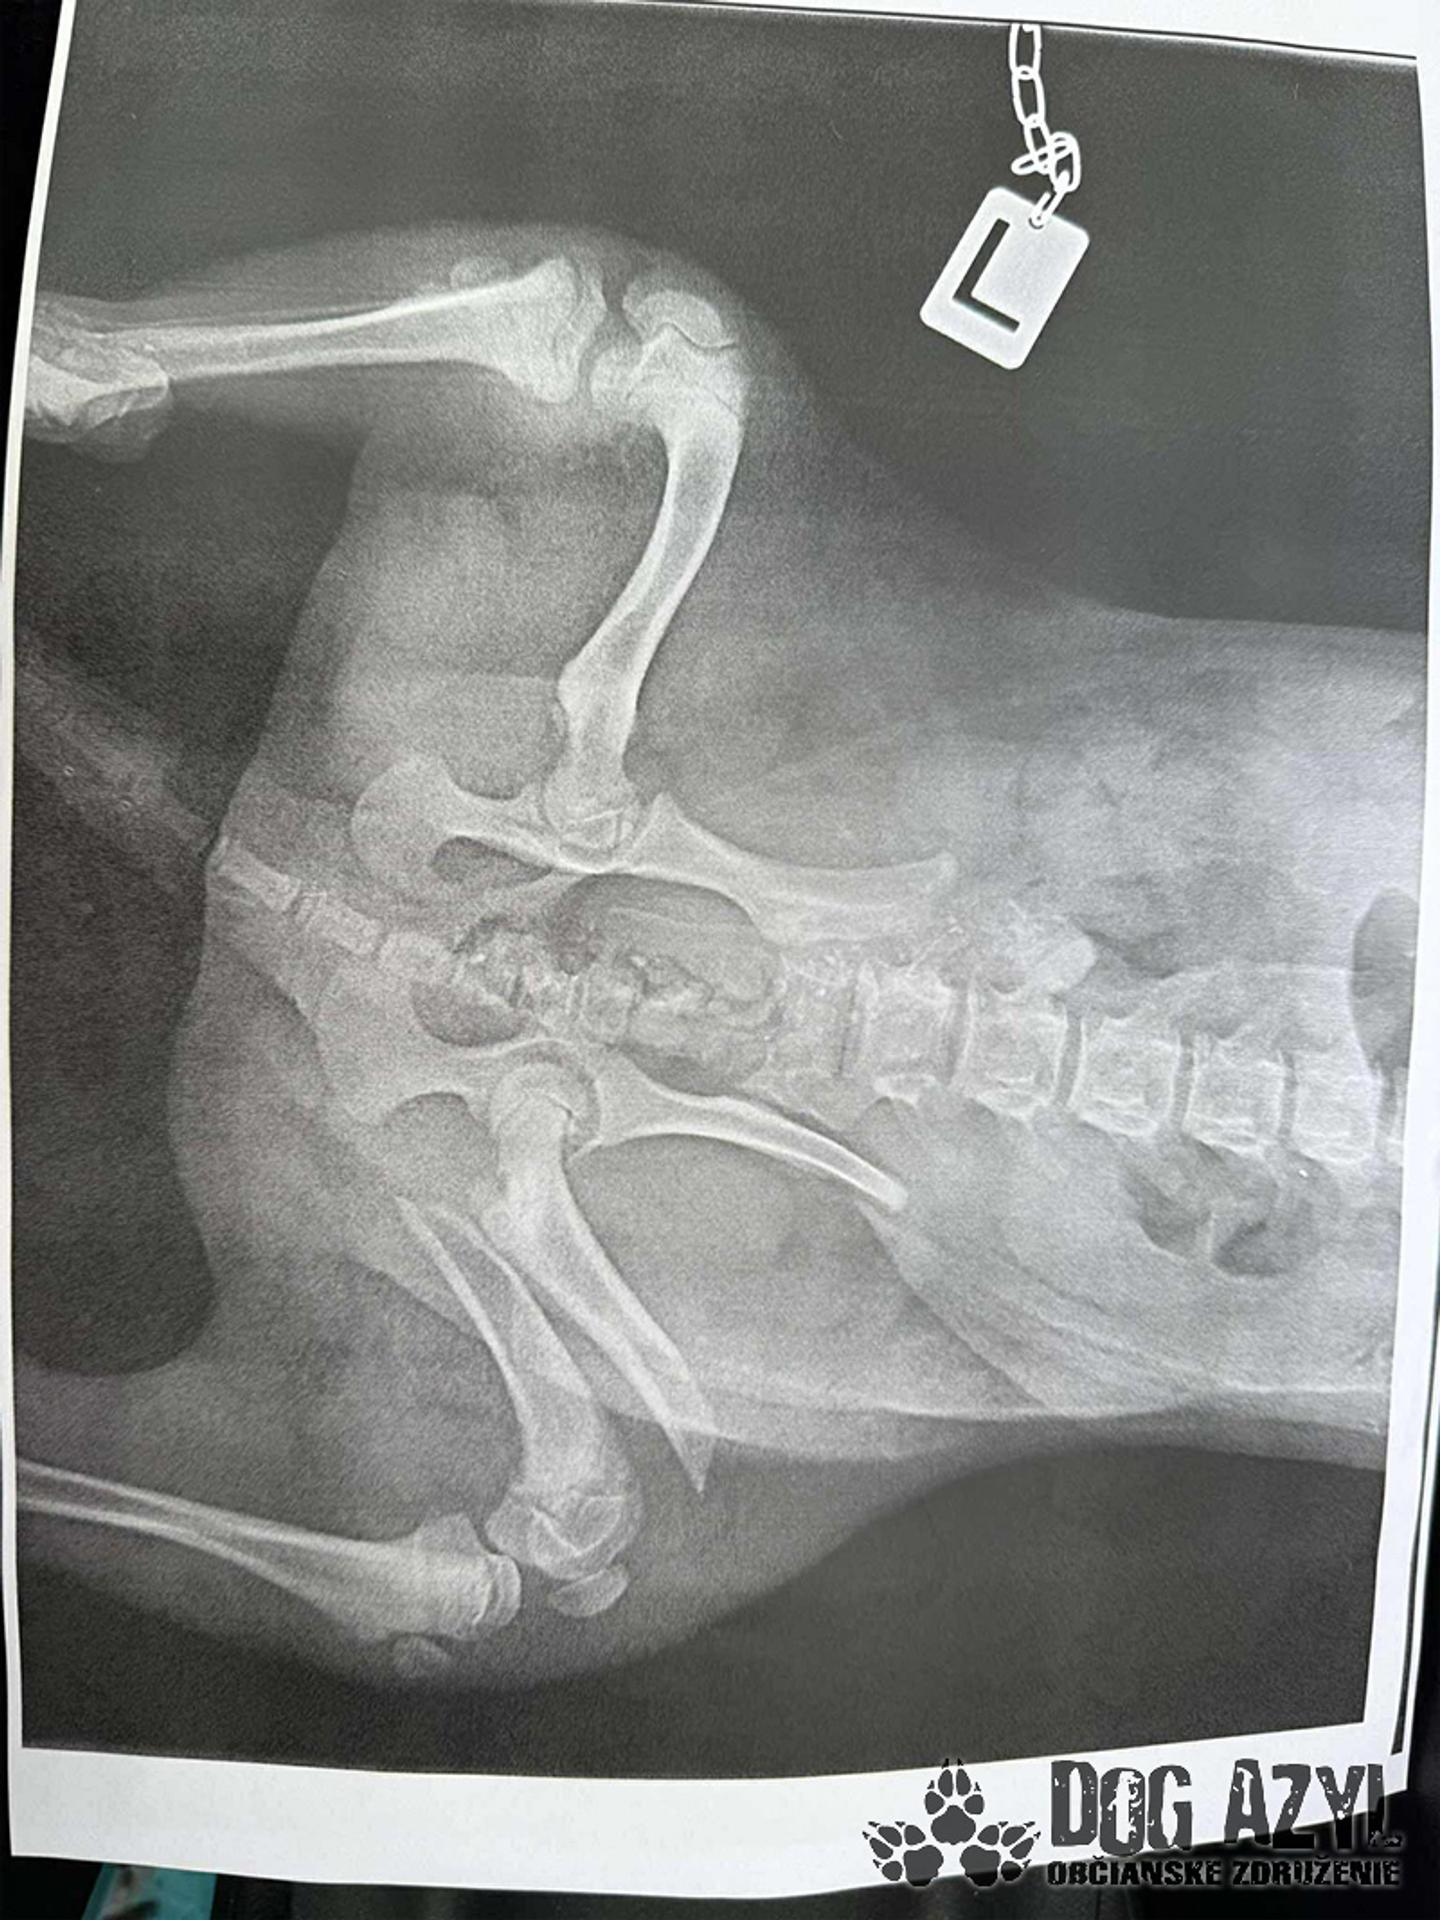

Týraný pes z Dunajskej Stredy

Zdroj: OZ Dog Azyl